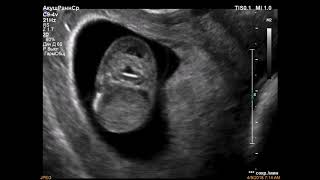

На 25 неделе беременности вес ребенка обычно составляет примерно 700 граммов. В этот период развития ребенок становится все более активным и начинает набирать вес.

25. неделя беременности